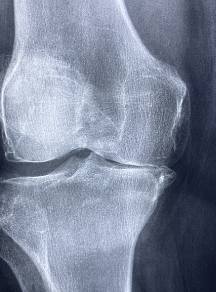

무릎 연골 손상 증상 원인 치료방법 등 무릎 연골과 관련된 정보를 알아보도록 하겠습니다. 무릎 연골 손상은 무릎 관절의 표면을 덮고 있는 유연한 조직이 부상, 과도한 사용, 연령 관련 마모 등으로 인해 손상되는 상태입니다. 무릎 연골 손상은 통증, 붓기, 움직임의 제한, 소리 발생, 불안정성과 약점 등의 증상을 유발할 수 있습니다. 무릎 연골 손상을 치료하는 방법은 다양하며, 손상의 정도와 개인의 상태에 따라 달라집니다.